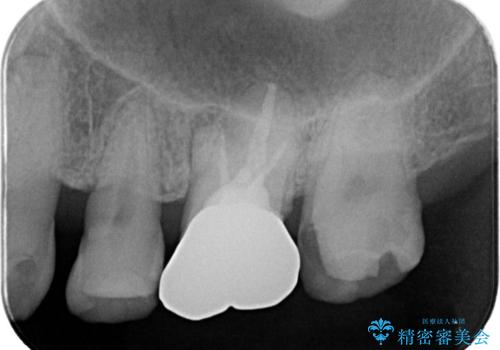

- 主訴:フロスを通したら、詰め物が取れた。適合の良いものを入れたい。

保険適用のメタルインレーが脱離しており、適合重視・咬合力が強いことからゴールドインレーでのやり替えとなりました。

フロスを通しインレーが脱離したことから、インレーと歯質との境に段差(適合不良)があった可能性があり、適合の良さや咬合力による補綴物の破折リスクを考慮し、ゴールドインレーでのやり替えとなりました。